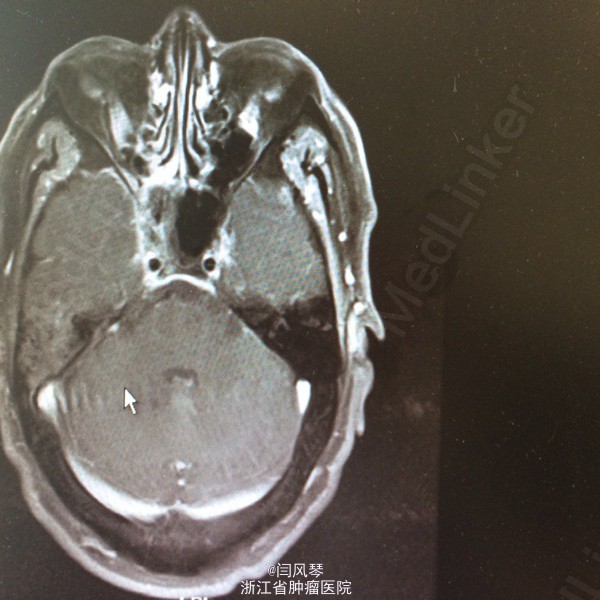

患者男,58岁,鼻咽癌放疗近2年,因鼻咽部复发于2015.6.12-2015.8.25于当地医院行TP方案化疗4周期,现化疗后1月余,诉右耳听力下降,右侧口角周围皮肤麻木感,为进一步诊治就诊于我院,门诊拟“鼻咽恶性肿瘤复发”收治。

一般可,生命体征平稳,鼻咽右侧壁及顶壁见新生物,双颈部未及明显肿大淋巴结。

诊断:鼻咽恶性肿瘤复发。治疗:复发灶局部放疗

讨论:患者鼻咽部放疗后复发,行4周期化疗后,肿瘤残留较明显,有局部放疗指征,但患者首程放疗后近两年,时间较短,再程放疗易引起鼻咽部溃疡大出血、放射性脑病、放射性神经损伤灯较严重的并发症,需积极预防及治疗